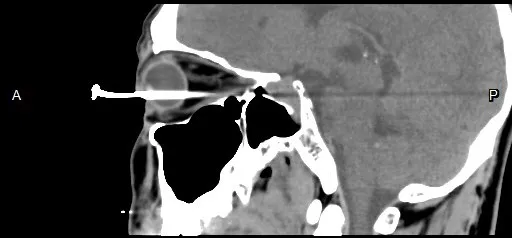

電腦斷層影像可看到男子右眼插著一根釘子,直達眼球的後方。李學宇醫師提供